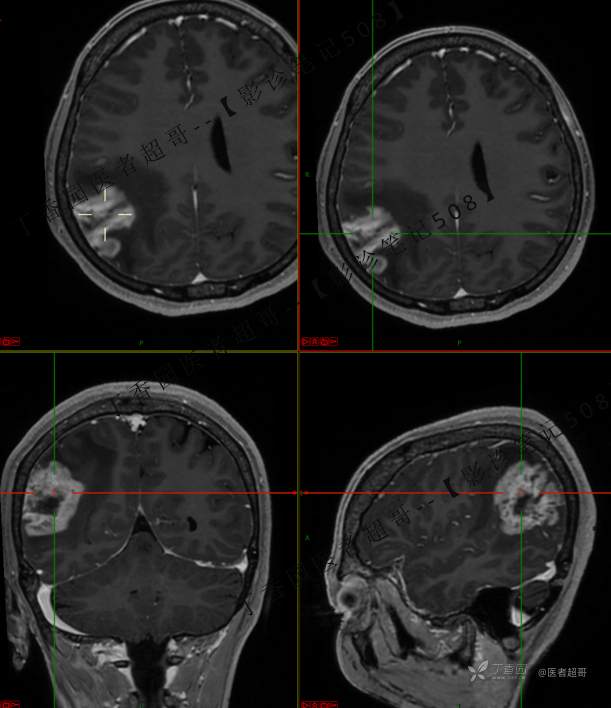

【影诊笔记508】同病异影,个人感觉有难度,欢迎分析,领丁当!有详细术程及病理!

患者性别:女

患者年龄:46岁

主 诉:突发一过性意识不清伴肢体抽搐5天余。

现病史:患者5天余前无明显原因及诱因出现一过性意识不清,伴肢体抽搐,持续约2-3分钟,后意识逐渐恢复,无明显头痛头晕,无恶心呕吐,无肢体抽搐,无呼吸困难,无二便失禁,后就诊于当地医院,行颅脑CT示“颅内占位性病变”,予以药物对症治疗,具体不详,门诊以“颅内占位性病变”,收入我科。患者自发病以来,未进饮食,近期体重无明显变化。